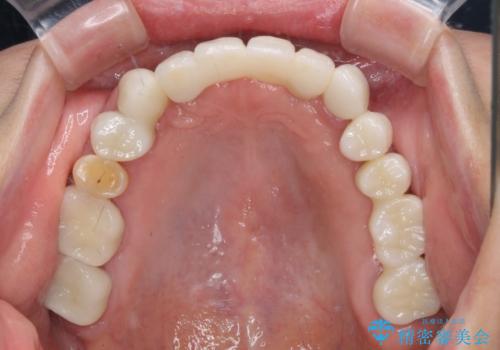

歯周外科処置を行ったことで歯周ポケットはなくなり、毎回のブラッシングの度に嫌な思いをしていた出血は認められなくなりました。

上下前歯の見え方を気にされており、歯だけをみると大変長くなりましたが、笑ったときの口元は自然な外見となり、患者様には大変満足していただきました。